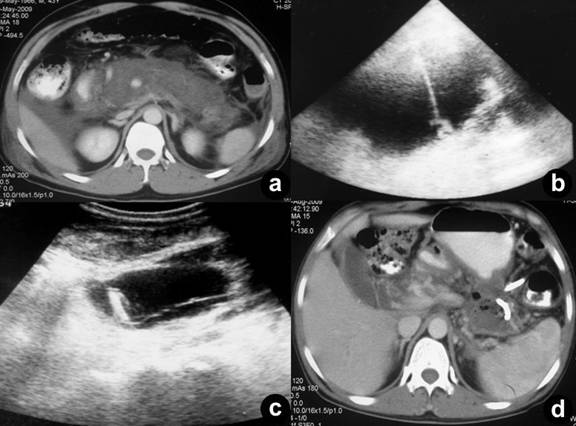

Twenty-four patients (48.0%) underwent image-guided drainage of the pancreatic/peripancreatic collections. Nine of these patients (37.5%) were successfully managed by radiological intervention only (Figure 2) while 15 (62.50%) continued to have or developed infection, persistent organ failure or locoregional complications. These 15 patients were subsequently operated upon (Figure 3). There were a total of 11 procedure-related complications in these patients (73.3%) with two patients having catheter slippage which required repositioning (Table 1).

Figure 2. a. CECT showing extensive necrosis at three weeks after the onset of gallstone-induced pancreatitis b. Fifteen days later ultrasound guided access into a fluid collection when a 10 Fr catheter was inserted. c. and d. Near total resolution after 6 weeks. No surgery carried out. |